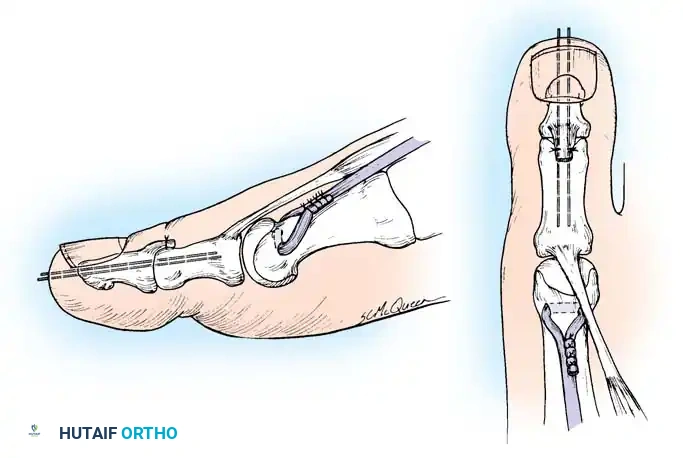

2. Jones Procedure (EHL to First Metatarsal Neck)

* Rationale: Corrects flexible clawing of the hallux and elevates the first ray.

* Technique: Transect the EHL at the IP joint. Reroute it through a drill hole in the neck of the first metatarsal and suture it back onto itself. The IP joint of the hallux must be arthrodesed to prevent a secondary drop-toe deformity.